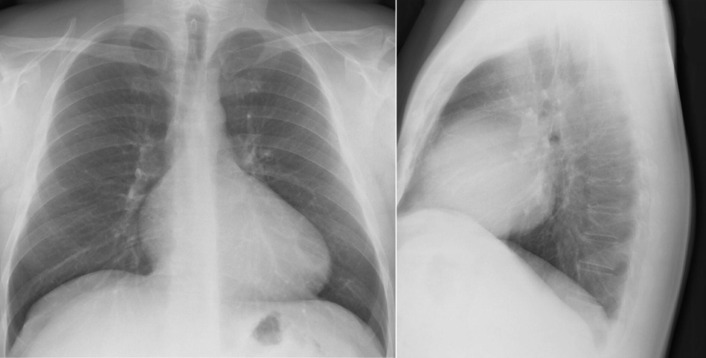

Ebstein’s anomaly. Note the moderate cardiomegaly, the prominence of the right atrium and right ventricle as well as the small main pulmonary artery.